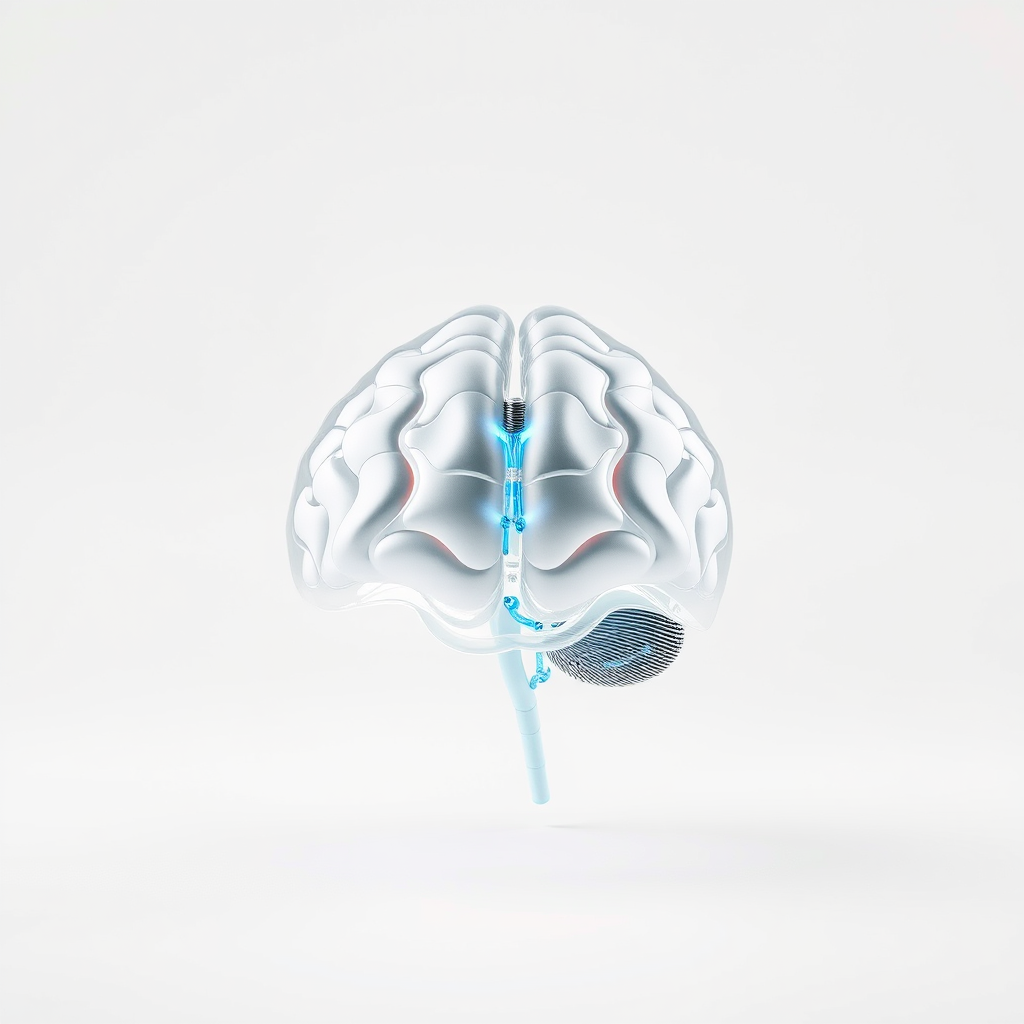

Técnicas de Reabilitação Neuropsicológica

Técnicas de reabilitação neuropsicológica são fundamentais para a recuperação de funções cognitivas em indivíduos que enfrentam desafios mentais e comportamentais.

A reabilitação neuropsicológica é um processo que envolve diversas etapas e métodos, todos focados na restauração das capacidades cognitivas e comportamentais.

Abordagens e Técnicas Utilizadas

Intervenções Personalizadas

Essas atividades são projetadas para estimular as áreas do cérebro que precisam de reabilitação, ajudando os pacientes a recuperar suas capacidades cognitivas e a melhorar sua qualidade de vida.